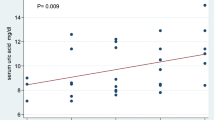

On femoral hyaline cartilage, the double contour sign (Figure 1A) was present in 17 of 100 knees from hyperuricemic patients in contrast to none in the control group (P < 0.0001), giving an odds ratio (OR) of 43.8 (95% confidence interval (95% CI), 2.9 to 739). The prevalence of the double contour sign in the first MTPJs (Figure 1B) was also higher in hyperuricemic patients (25% vs. 0%; P < 0.0001), with an OR of 34.3 (95% CI, 4.5 to 259). However, no correlation between SU concentration and the presence of the double contour sign was found (rs -0.06; 95% CI, -0.3 to 0.2).

Tophi formation was found in 18 individuals with hyperuricemia but in none of the normouricemic controls (P < 0.0001), producing an OR of 46.8 (95% CI, 2.7 to 789); however, mean SU concentrations were similar regardless the presence of tophi (8.13 ± 0.89 vs. 8.13 ± 0.99 mg/dL; P = NS). Intra-articular tophi were found in eight (8%) hyperuricemic patients but in none of the normouricemic controls (P = 0.003).

Tendon examinations showed patellar enthesopathy (12% vs. 2.9%; P = 0.01) and intratendinous tophi (6% vs. 0; P = 0.01), as well as Achilles enthesopathy (15% vs. 1.9%; P = 0.0007), to be more frequent in hyperuricemic patients than in normouricemic individuals (Table 3). Tenosynovitis was found only in three hyperuricemic patients (two in the peroneus longus tendon and one in the posterior tibialis tendon). No PD signal was found in any anatomical area examined.